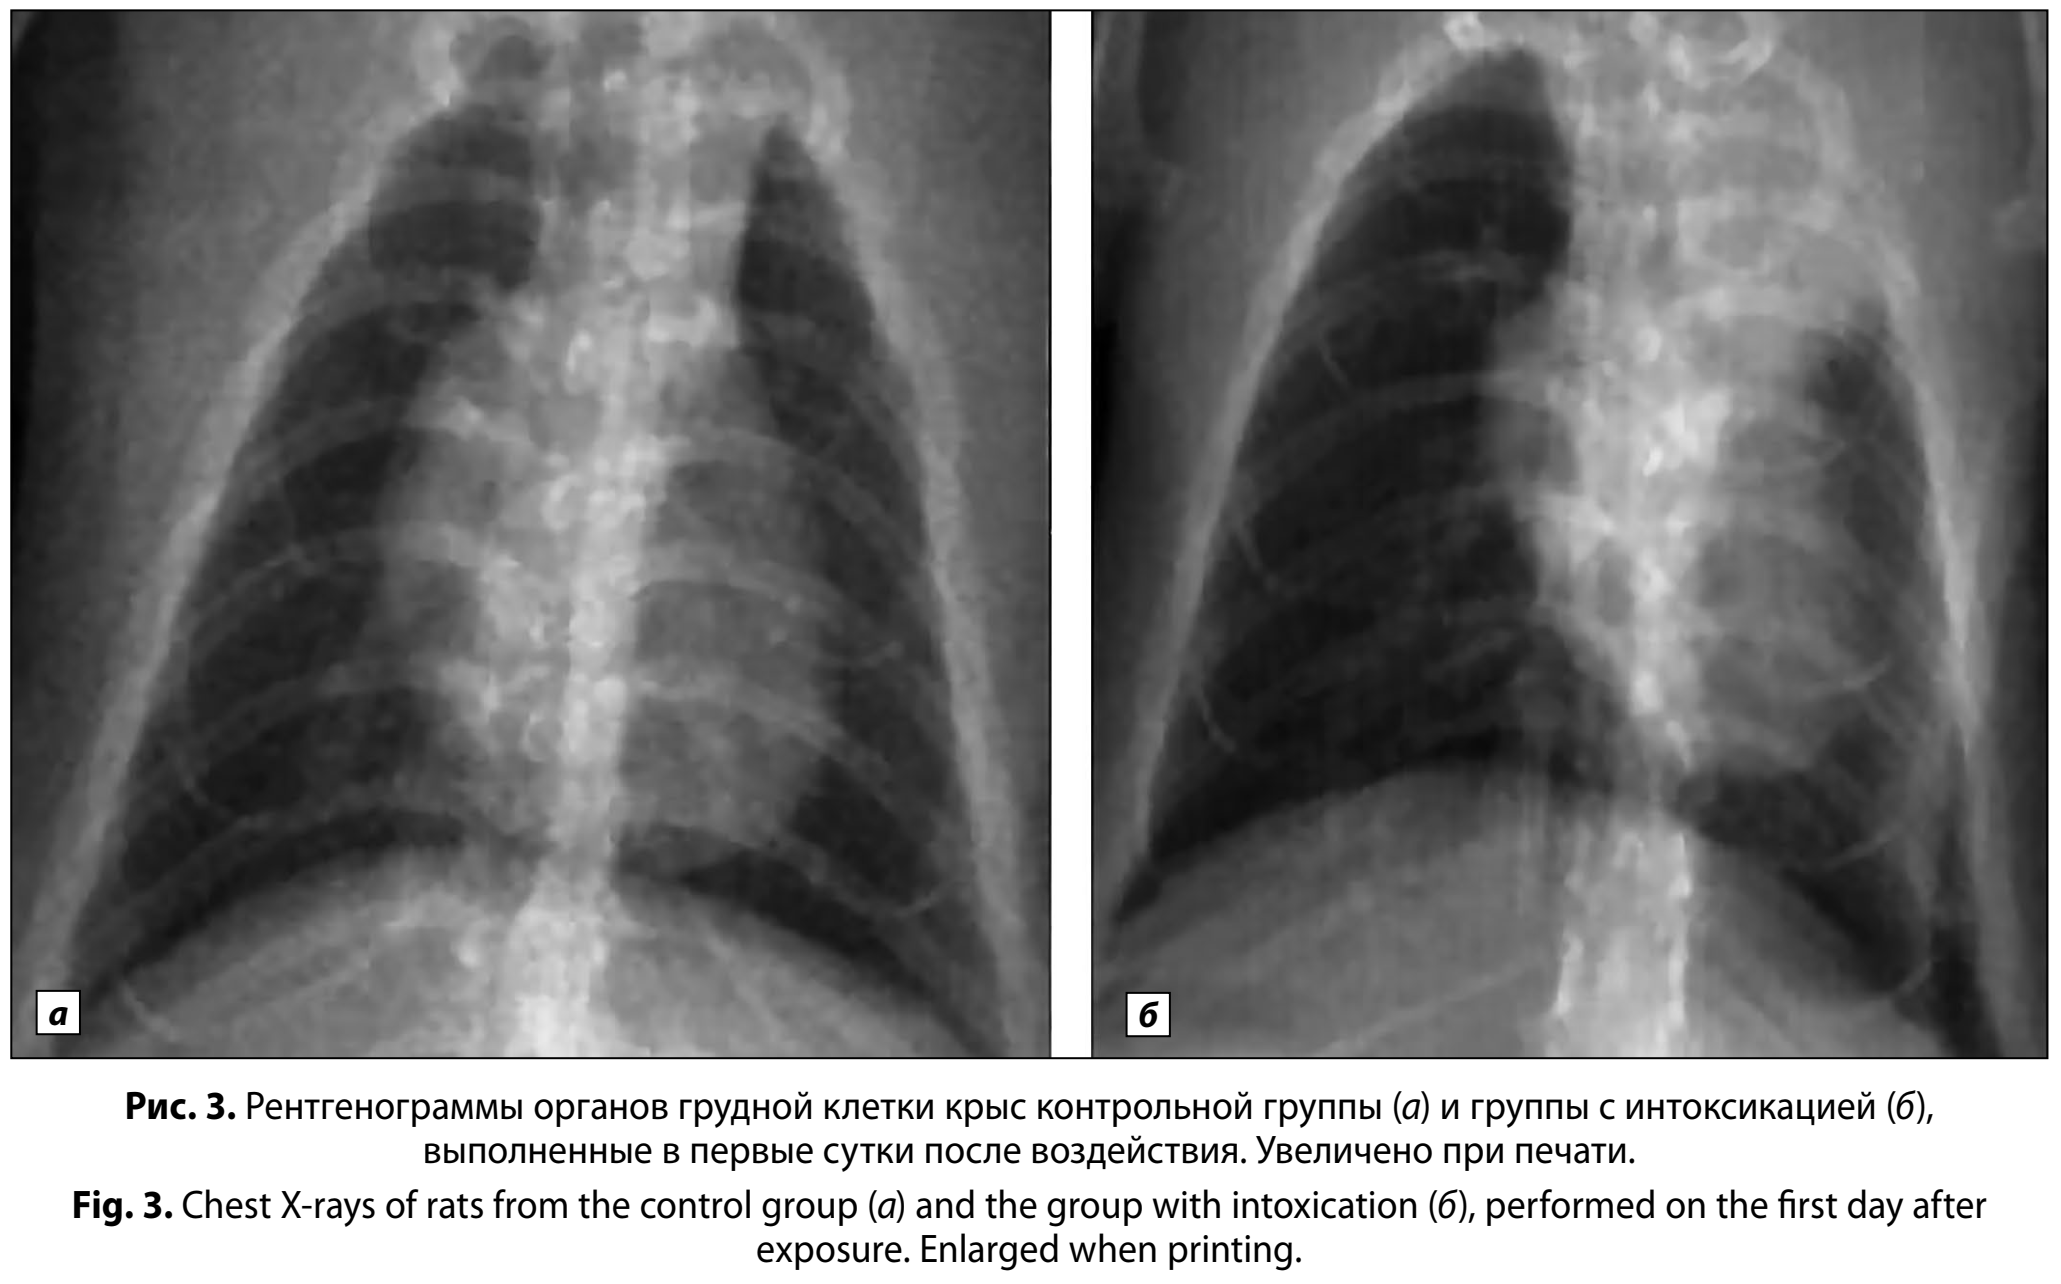

При проведении анализа рентгенограмм, полученных после воздействия, выявили значимые (p < 0,01) различия в частоте встречаемости очаговой инфильтрации у животных, подвергшихся воздействию бензина, по сравнению с животными контрольной группы. На 1-е сутки у 20 ± 9% животных группы с интоксикацией наблюдали усиление лёгочного рисунка с очаговой инфильтрацией в верхних сегментах лёгких, тогда как в контроле патологические изменения отсутствовали (рис. 3, а, б). К 5-м суткам доля особей с рентгенологическими признаками поражения составила 50 ± 12% и была выше (p < 0,001) по сравнению с контролем (рис. 4, а, б).